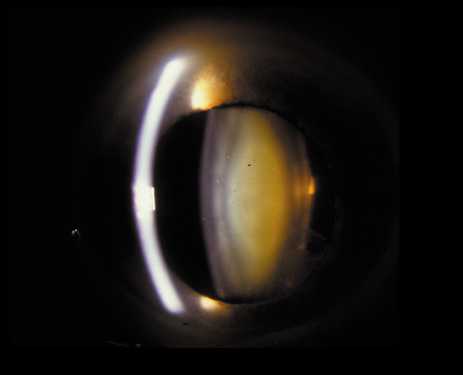

One can examine this type of cataract with direct illumination, using the narrow and broad beams of the slit-lamp to show the characteristic granular inner surface immediately in front of the posterior capsule (Fig. 13). The problem with this technique, however, is that patients may not tolerate any prolonged direct illumination because of the glare. Retroillumination is therefore more useful for revealing the outline of the opacity, since it is usually seen as an “island” in the center of the posterior capsule, which is further highlighted by the shadow cast by the opacities.33 However, in the early stages of this type of cataract, the dust-like particles that might be noticeable in the central posterior subcapsular area with direct illumination disappear or are difficult to see with retroillumination (Fig. 14). Eventually this “dusting” becomes dense enough to cast a shadow and thus appear on retroillumination. The smooth orange background of the fundus helps to highlight the rough, irregular pseudopodia-like edges of the central opacity. In advanced stages, the PSC may become a thick, calcified plaque (Fig. 15). During surgery, excessively vigorous scraping or vacuuming of the calcified opacity can lead to rupture of the posterior capsule. Usually, small remnants that are left behind after surgery are reabsorbed and do not interfere with vision; otherwise, they are easily treated with a neodymium : yttrium (Nd:YAG) aluminum garnet laser. Pathologic evidence suggests that most PSCs result from the migration of bow region cells into the potential space (along with accumulated cellular debris) between the posterior capsule and the cortex.34–36

Fig. 13. Direct slit-lamp illumination of a PSC, showing an irregular granular surface in front of the posterior capsule.